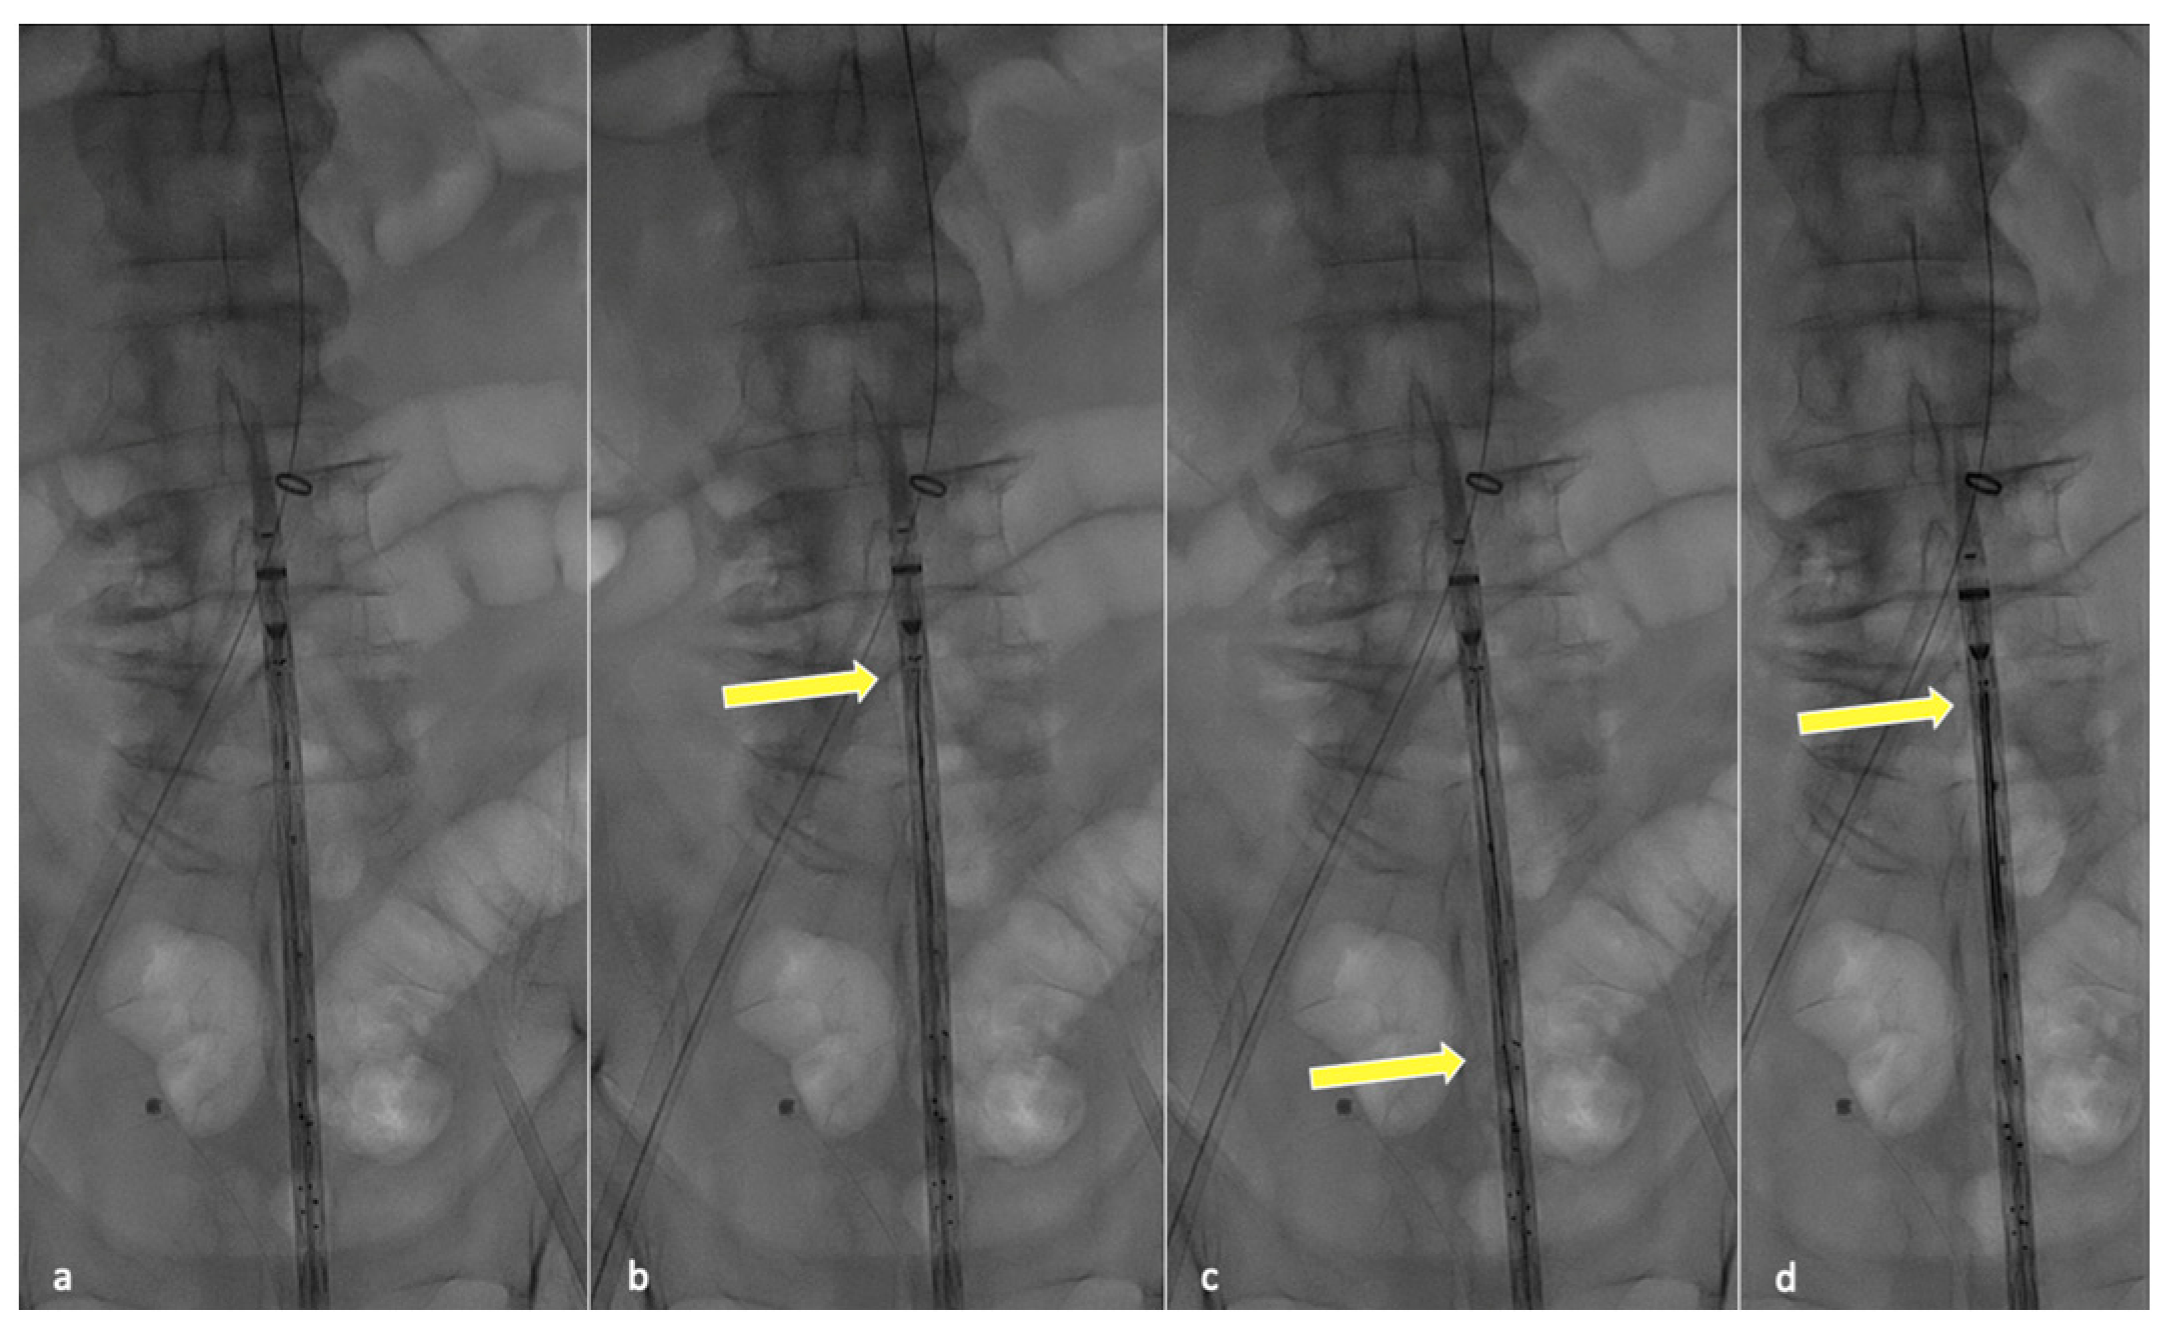

The proximal clasping mechanism is then released, fixing the endograft position, and visceral vessel bridging is completed from the upper access, establishing and taking advantage of the through-and-through. The distal portion of the endograft is completely released after revascularizing one or more target arteries, depending on preoperative planning and the expected hindrance level for target vessel cannulation.

Preventing the distal end of the graft from fully expanding simplifies visceral vessel cannulation maneuvers and bridging component advancement, especially when dealing with restricted lumina (Figure 2). This aspect is even more critical when using an E-nside graft compared to outer-branched devices, given that while the middle portion of the endoprosthesis measures 24 mm in diameter, its distal segment re-expands to 26 or 30 mm with a reverse tapering. The partial deployment approach prevents this distal segment from filling up the inner aortic lumen at the renal artery ostia, a condition dependent on the graft deployment height, potentially leading to target vessel occlusion.

Figure 2. Angiographic images from a case performed using the described technique. Circles indicate visceral vessels origin (positioned using fusion technology). By maintaining the distal endograft constrained into the delivery system the available space for cannulation and bridging components advancement increases. In panel (a) the left renal bridging stent has just been released, the arrow is pointing at the three remining pre-positioned 0.018″ pre-cannulated guidewires. In panel (b) the superior mesenteric artery bridging stent is correctly positioned and ready to be deployed.